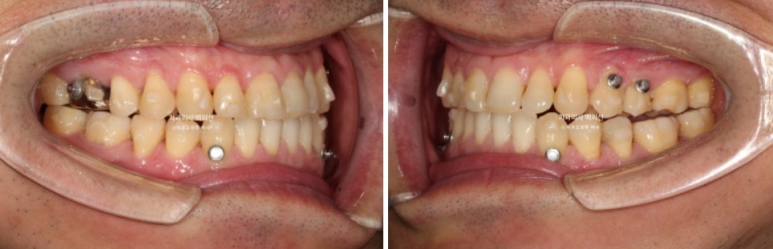

24.10

교정용 나사인 미니스크류를 아래쪽에 2개 심고 3급 고무줄을 걸며 치료를 진행중입니다.

치료시작 10개월차 첫세트의 장치를 모두 낀 후 모습입니다.

큰 공사는 끝났으나 미진한 부분들이 보입니다.

앞니 반대교합은 해결 되었으나 여전히 중심선이 미세하게 안 맞고

어금니 교합이 뜨는 부분이 있어 24년 10월 재제작에 들어갔습니다.